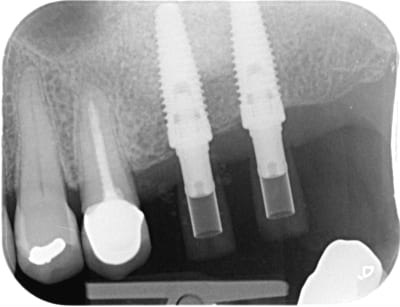

Une astuce pour faire une empreinte optique après pose des implants en vue d’une mise en charge dans les heures qui suivent l’intevention .

Pour usiner un bridge PMMA direct multi unit, ou autre , selon les possibilités du Prothesiste .

Le peu de repères chez l’édenté complet , surtout en bas , les scanbodys qui se ressemble et font sauter la caméra , l’espace entre les scanbody, tout cela rends l’empreinte optique peu pratique en MCI.

L’idee est d’utiliser les forages des clavettes du guide chair pour placer un scan-guide.

Celui ci permet alors de s’isoler du sang , de donner des repères pour le scanner et le matching avec le projet prothétique.

J aime bien ta technique de "salir" avec silicone light pour que la cam se retrouve mieux ou les sphères de ton guide.

La digue neutre + tous les scanbodies identiques... A mon avis la caméra n accroche pas bien et saute... Voir se raccroche a un autre endroit.

Le light permet de faire un repère pour fixer la cam sur le bon chemin.